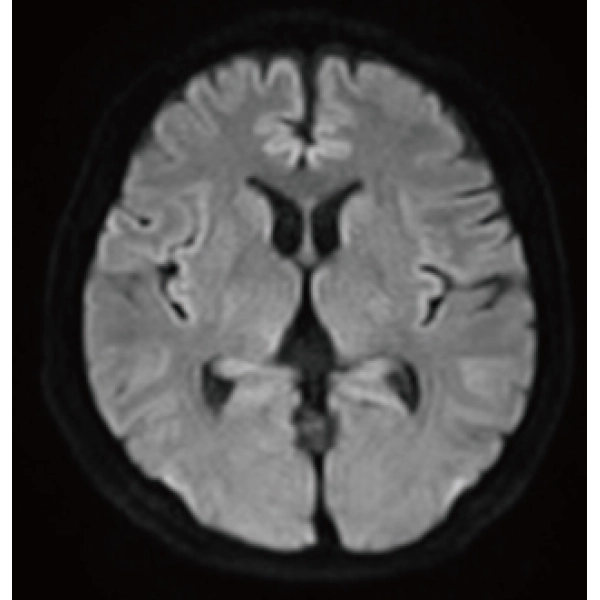

"DLR" is applicable to all body parts and promotes high speed imaging and diagnostic efficiency

IP-RAPID x DLR Plus can also shorten imaging time, allowing more images to be taken in the same examination time.

Additional imaging, such as different image types and cross sections, can be added to the conventional examination to increase the amount of information and make the diagnosis more reliable.

Deep Learning technology*8 enables image quality adjustment after imaging is complete. It optimize SNR and improve image sharpness by processing MRI signals in stages (k-space signal processing). This brings super-resolution and reduces truncation artifacts.